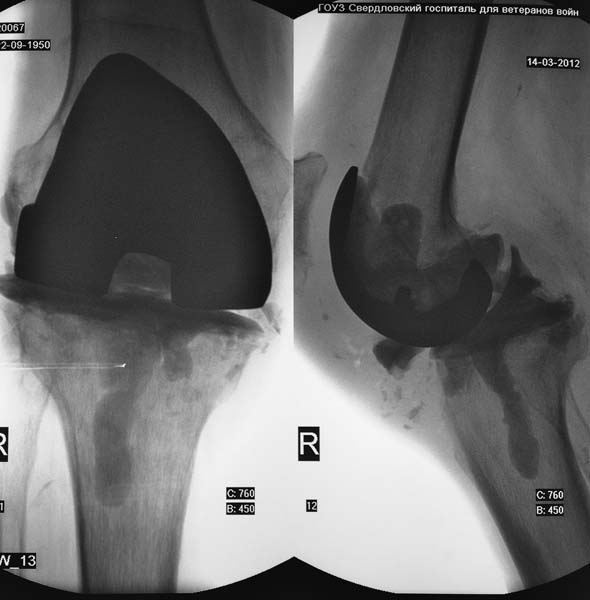

Уважаемые коллеги! Пациент мужчина 62 года эндопротезирование коленного сустава в

сентябре 2011 в одном из соседних учреждений. Множественные операции по восстановлению

связок в анамнезе

Под наше наблюдение попал спустя 3 месяца с клиникой глубокой перипротоезной инфекции.

Гнойный свищ, MRSA в посеве. Выполнено удаление протеза, некрэктомия, установка

цементного спейсера. Заживление первичное, а\б терапия по посевам, в течении 2 месяцев

положительная динамика, нормализация лабораторных показателей. В последующем усиление

болей, отек, разрушение спейсера по рентегнограммам. Взят в операционную для повторной

некрэктомии, удаления спейсера. Во время операции выявлено- отсутствие явного гнойного

содержимого, ткани более жизнеспособные чем во время первого удаления, отсутствие

значительного прогрессирования костных дефектов. Решено от одномоментного артродеза

воздержаться, конечность стабилтзирована дистракционным аппаратом. В

интраоперациооных посевах St.aureus В настоящее время две недели после операции, встает

вопрос о возможностях далнейшего лечения. Ревизонное колено? Еще раз после спейсера или

сразу? Или артродез